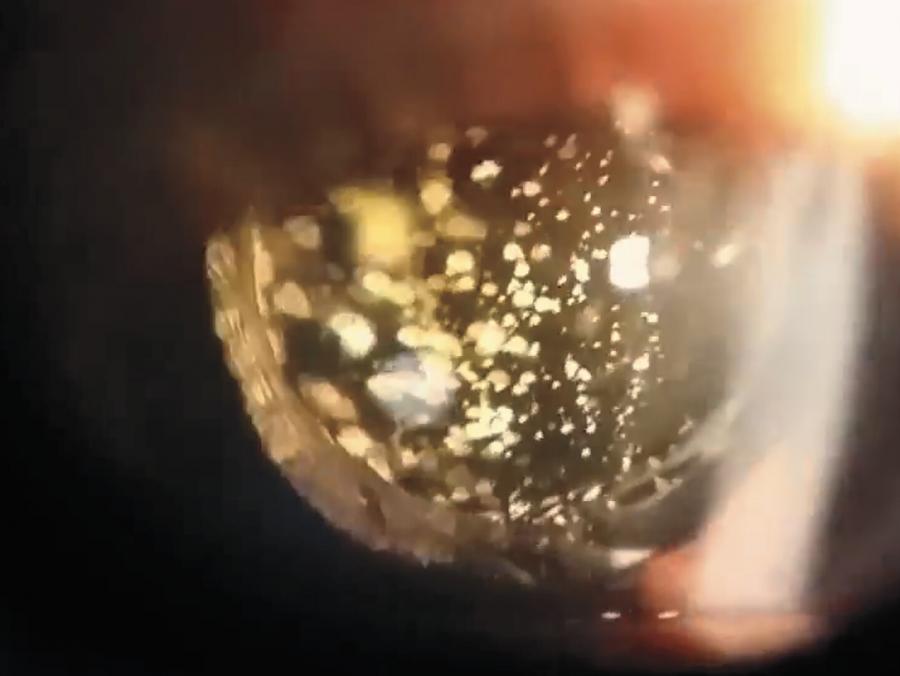

През 2018 г. например при 54-годишна жена с диабет, която отишла на рутинен очен преглед, бил открит учебникарски случай на АХ в лявото ѝ око, както може да се види по-долу. Тя не е осъзнавала, че то е там.

Други видове отломки са невидими за човека, но изглеждат като "искрящи мътнини" за онези, които гледат към очите му. При пряко осветление тези астероидни тела са "кремавобели". Но при използване на офталмоскоп - устройство, което позволява на лекарите да надникнат във вътрешността на окото, материалът блести като злато.